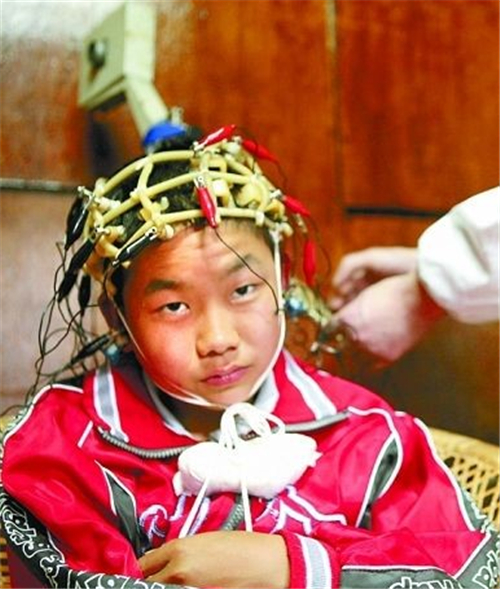

中醫治療腦萎縮

外傷引發的腦萎縮治療

先天性腦萎縮